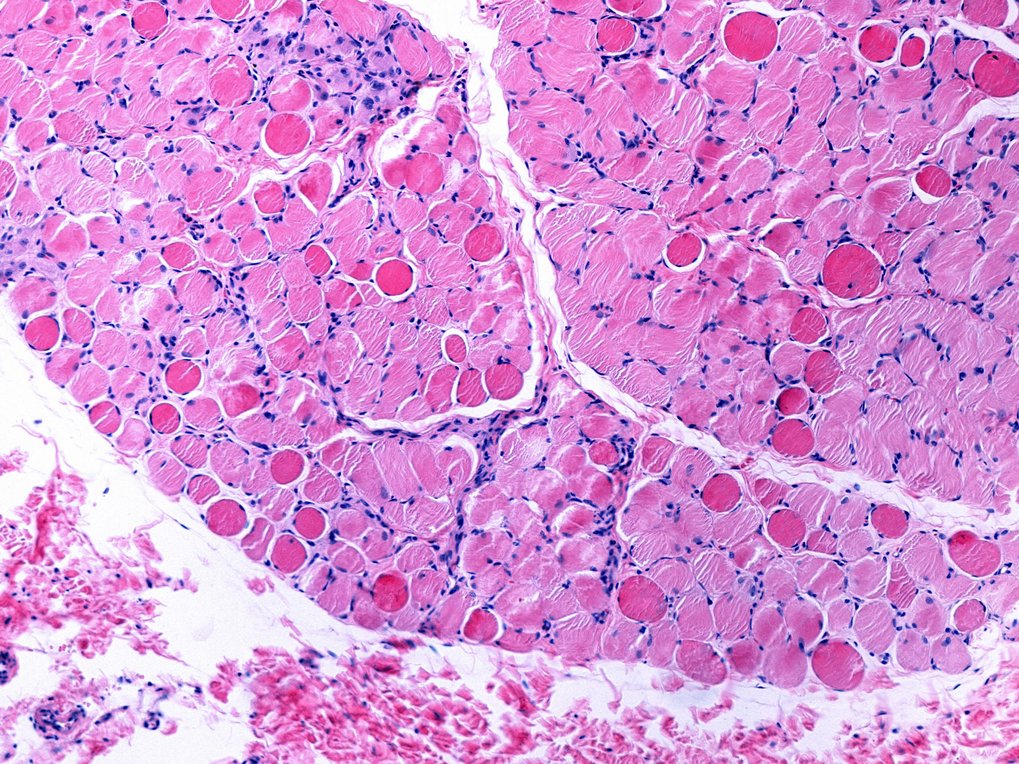

Während der Entwicklung des Embryos durchläuft das Herz kritische molekulare und strukturelle Veränderungen, die es für eine lebenslange Schwerstarbeit fit machen. Nach der Geburt stoppt die Vermehrung der Herzzellen und es werden zusätzliche Zellkerne gebildet. Gleichzeitig werden die kontraktilen Einheiten, die Sarkomere, innerhalb der Herzmuskelzellen steifer. Störungen oder Fehler in diesem Reifungsprozess sind häufig mit angeborenen Herzfehlern verbunden. Um diese zu verhindern, ist ein detailliertes Verständnis der molekularen Mechanismen, die der Reifung von Herzzellen zugrunde liegen, unerlässlich.

Aber welche molekularen Prozesse werden durch Spleißproteine gesteuert? „Unsere Studien haben gezeigt, dass RBPMS und RBPMS2 eine Schlüsselrolle bei mehreren grundlegenden Prozessen der Herzentwicklung spielen”, so Lin. Die Gruppe entdeckte, dass RBPMS und RBPMS2 nicht nur die Bildung von Isoformen für Proteine des Sarkomers steuern, sondern auch die Bildung des Spindelapparats regulieren, der für die Zellteilung unerlässlich ist. „Wenn beide Proteine inaktiv sind, ist die Zellteilung gestört“, erklärt Lin.